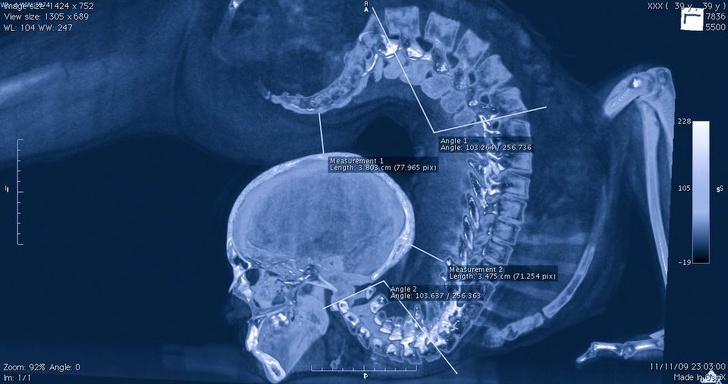

4. Комп’ютерна томографія гімнастки, що виконує вправу

20 знімків, які раніше бачили тільки рентгенологи. А тепер можете і ви